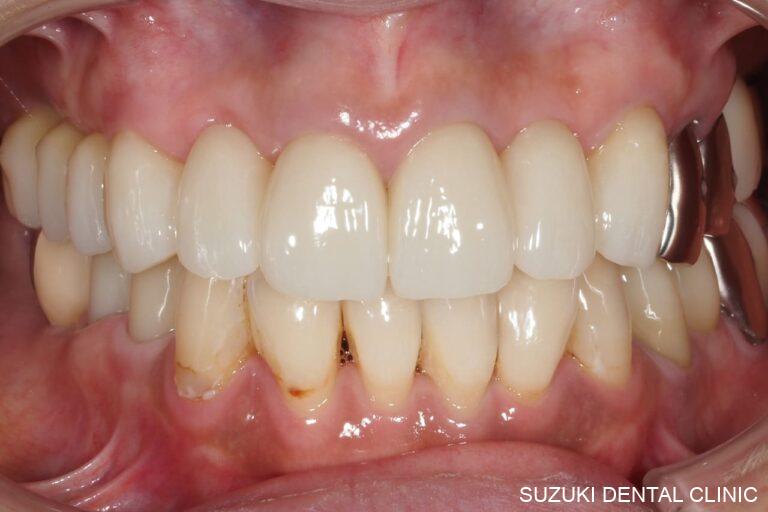

特に追加治療を行う際の、謂わば、“プランB”を必ず治療計画時にご提案します。現在では精密歯冠補綴治療により歯周組織学の観点から長期予後を得られる方法が確立されつつあります。前述の治療はすべて手術用歯科顕微鏡(以下、マイクロスコープ)を用いた超精密かつ最小限の歯の切削と厳密な接着操作により、歯科材料の持つ性質を最大限に引き出して、生体親和性が高く、長期にわたり痛みや再治療リスクの少ない修復治療を実現する事にこだわりを持って臨床に臨んでいます。

これまでの臨床経験による技術と、咬合理論を駆使して、機能と審美性を兼ね備えた美しい口元と快適な食生活を取り戻すことは、患者のQOLを高めると共に我々の存在意義を同時に揺るぎないものとすることと確信しています。

歯周病治療・インプラント治療は私の専門分野の一つでもあります。歯周病学の病理組織学的基礎から基本治療、外科治療に至るまでの内容を網羅しており、歯周治療の考え方と技術・経営学を徹底的に教え込まれました。この経験を活かし、生涯の中で長期安定した予後、しっかり噛める喜び「キレイで長持ち」を患者と共有できることを喜びとして、日々の診療を行っています。